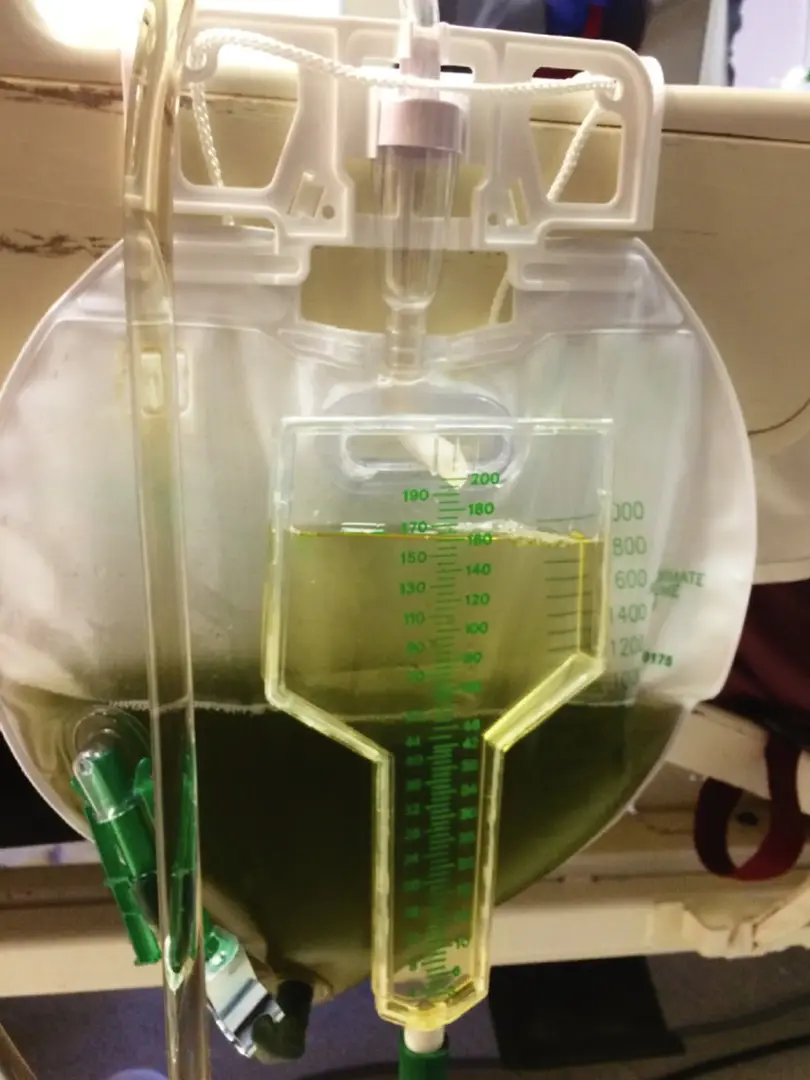

Caso muy ilustrativo publicado en Kidney 360 (enlace). Paciente de sexo femenino de 43 años con antecedentes de nefritis lúpica (NL) proliferativa durante 13 años. La paciente tenía un historial de enfermedad grave, con múltiples tratamientos que incluyeron infusiones de metilprednisolona y ciclofosfamida debido al compromiso del sistema nervioso central (SNC) y de la NL.